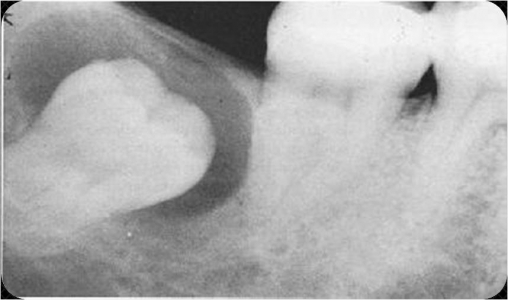

Dentigerous Cyst

Cyst tht originates by separation of the follicle from the crown of unerrupted tooth.

Accumulation of fluid between the REE and tooth crown

Follicular space is larger than 3mm

Encloses the crown of the unerrupted tooth and is attached at the CEJ

Completely asymptomatic – discoveredon routine xray

XRAY: UNILOCULAR radiolucency, well defined (sclerotic border)

Most commonly associated with 3rd molars

MOST COMMON DEVELOPMENTAL ODONTOGENIC CYST

Treatment: Enucleation of the cyst with the unerrupted tooth.

May marsupialization